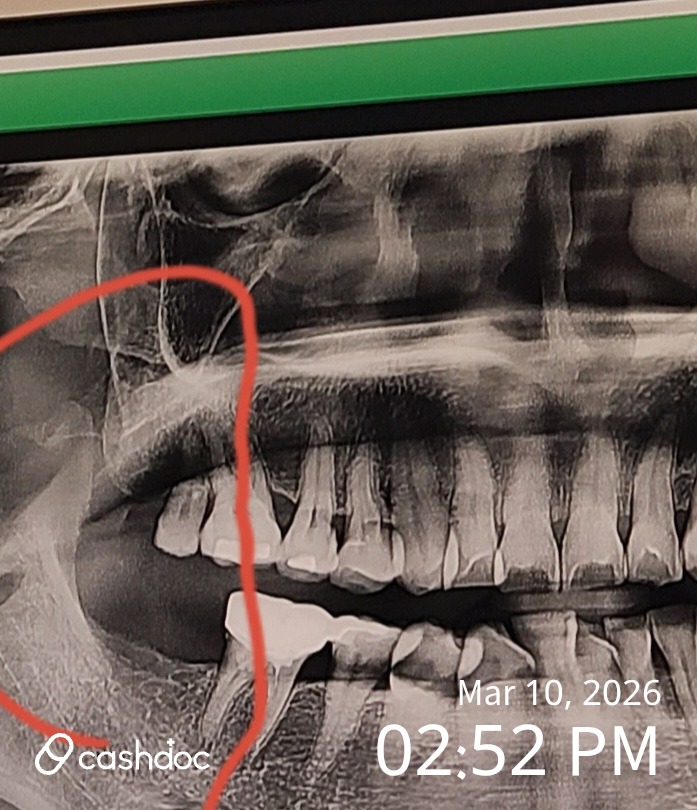

작년 초부터 한 임플란트 후기를 하려고 합니다. 보통 다들 임플란트 한다고 하면 길어봤자 3개월~4개월 얘기하는데 전 임플란트 식립까지 7개월정도 걸렸네요ㅜ.ㅜ 작년 초쯤 10년쯤 전에 씌운 어금니가 갑자기 흔들려서 뭐가 잘못됐지 싶어서 집근처 바르게고치과를 방문하였습니다. 저희 가족 전부가 여기 다니거든요. 그래서 안되면 다시 씌어야 겠구나라는 생각으로 방문해서 진료를 보니 선생님이 이빨이 삭아서 씌운부분이랑 통째로 부서질것(?) 같다고 하시더군요.... 뭔 이빨이 부서지지 하는데.. 의사선생님이 이빨을 잡고 살짝 힘을 주는 순간 이빨이 말그대로 반으로 부러지던군요ㅜ.ㅜ 이게 신경치료를 한 이빨은 썩어도 아프지가 않아 이렇게 된다고 하셔서 놀랐고 선생님이 씌울 부분이 없어서 발치를 하고 임플란트를 해야할것 같다고 하셨습니다.... 그래서 어쩔수가 없이 발치 날짜를 잡고 일주일후 발치를 했는데 설상가상 식립할 뼈가 많지 않아 골이식도 같이 병행해야 할듯하다고 하시더군요.... 그래서 발치후 골이식(이종골)을 했고 탄툼이라는 가글액을 처방해주셔서 가글을 발치후 꽤 오래했습니다. 근데 발치는 생각외로 많이 아프지 않았었습니다. 추후 2달뒤에 뼈 차는건보고 충분히 차면 하자고 하셔서 봤는데 생각외로 많이 안 차있다고 1달뒤에 다시 보자고 하셔서 다시 봤는데 그때도 안되고...... 결국 3번 더 본후 6개월 뒤쯤 이제는 되겠다며 1달뒤로 식립 날짜를 잡았습니다. 나이가 들면 더 뼈가 잘 안찬다고 하더라구요... 나이든것도 서러운데.... 참고로 저는 오스템 BA로 했습니다.. 스트로우만은 넘 비싸서 엄두도 못내겠더라고요 그래도 선생님이 워낙 꼼꼼하셔서 다행이었어요~~ 요새는 원데이 임플란트라고 발치하고 곧바로 임플란트 한다는데 전 급하게 해서 오래 안가는 사람들은 너무 많이 봐서 차라리 내가 귀찮더라도 꼼꼼히 하는게 더 좋았습니다. 식립일 당일 발치후에 그렇게 아프지는 않았어서 그렇게 긴장도 하지 않았고 드뎌 임플란트를 하는구나라고 생각하며 오히려 후련하기도 하였습니다^^ 그래서 장장 두시간에 걸쳐 수술을 잘 끝내고 유의사항이랑 이것저것 약 처방후 집에 왔습니다. 근데 이건 왠걸 진통제를 먹었는데도 너무 아파서 하나를 더 먹었음에도 전혀 나아지지가 않았고 더욱 더 아파지기 시작했습니다...... 그래서 끙끙대며 밤을 꼬박새우고 병원을 다시 가봐야겠다고 생각한 아침쯤부터 통증이 잦아들기 시작하더군요... 너무 힘들어서 회사에 휴가를 내고 그날 하루를 쉬었고 그렇게 임플란트 식립까지 무사하게(?) 마치게 되었답니다. 임플란트 종류를 선택할때 종류도 워낙많고 가격대도 너무 다양하여 선택하기가 너무 힘들어서 공부를 엄청 많이하고 선택을 했었습니다. 임플란트는 어차피 평생 쓰지는 못하고 소모품이기 때문에 최대한 오래쓰는걸 목적으로 해야합니다. 그래도 잘하는 치과를 고르는게 가장 중요합니다^^ 임플란트 종류 및 좋은 치과를 잘 고르는 방법을 공유해드립니다!! 먼저 임플란트 구성 종류를 설명드리겠습니다. 이건 종류가 너무 많아서 처음에 치과에 설명해주시는데 아무것도 몰라서 집에서 이틀정도 공부해서 선택한 기억이 있습니다. 치과에서도 그렇게 자세히 설명해 주지 않으시던군요ㅜ.ㅜ 제가 공부한 한도에서 자세히 설명드리겠습니다^^ 임플란트의 구성 임플란트는 크게 세부분으로 나뉩니다. 위 사진처럼 뼈에 박는 나사같은 부분이 고정체(픽스처)라고 합니다. 임플란트에서 종류별 가격대가 틀려지는게 바로 이부분이라고 할 수있고 가장 중요한 핵심적인 부분입니다. 그 이유는 골유착이 잘 이뤄지느냐가 임플란트 오래 쓸수있는 핵심이기 때문이죠 그리고 중간에 보철물과 고정체를 연결해주는 지대주(어버먼트)가 있습니다. 마지막으로 우리가 씹는 머리부분인 보철물(크라운)이 있습니다. 우리치아와 같이 음식물을 씹는 역할을 하는 부분이고 보통 우리치아랑 유사한 지르코니아로 많이 하십니다. 저도 지르코니아로 했습니다 ㅎㅎ 임플란트의 종류 및 가격대 먼저 상대적으로 저렴한 가격대로는 오스템, 덴티움, 네오, 메가젠 등이 있으며 상대적으로 비싼 가격대로는 스트로우만, 아스트라, 덴마, 노벨바이오케어 등이 있습니다. 대체적으로 저렴한 가격대는 국산들이 차지하고 있고 비싼 가격대는 외국산들이 많더군요~ 저는 대중적인 오스템으로 해서 오스템만 공부했습니다^^;; 죄송합니다. 오스템 모델별로 특징을 알려드리겠습니다~ 가격대는 아래쪽으로 갈수록 비쌉니다. 참고하세요~ 모델 등급 특징 비고 SA 보급형 일반적인 보급형 제품으로 임상데이터 다수 보유, 치조골 양호한 경우 적용 CA 보급형 SA와 비교하여 한단계 업그레이드된 제품으로 SA표면에 칼슘용액을 더해 초친수성 표면처리를 하여 혈액 젖음성을 향상, 치조골 양호한 경우 적용 BA 프리미엄형 뼈와 유사한 성분을 나노코팅한 표면처리로 골유착 성능 향상, 치료기간 단축, 다양한 골질에 적용 SOI 프리미엄형 2017년 출시하였고 특수물질을 코팅한 차세대 표면처리로 혈액 형성을 촉진시켜 골유착을 빠르게 진행, 치조골의 재생속도 빠름, 치료기간 단축, 약한 골질에도 사용가능 여기서 간단한 용어만 설명드리면 치조골은 임플란트를 식립할 뼈를 얘기하고 골유착은 그 뼈와 임플란트 고정체간의 융합을 말합니다. 골유착이 좋으면 임플란트를 오래 쓸수 있겠죠^^ 저같은 경우는 치조골이 많지 않고 생성중이라 요새 많이 쓰는 BA로 했습니다. 요새 보통 치과에서는 BA등급으로 많이 하시는것 같습니다~ 다음으로 임플란트 자체도 중요하지만 더 중요한 시술을 할 치과를 선택하는 방법입니다^^ 첫번째. 의사의 경험과 자격 임플란트를 전문으로 하는 의사의 경험과 자격입니다. 그리고 최신 시술방법에 대하여 잘 알고 있고 트렌드를 잘 아는것이 중요합니다! 임플란트도 최첨단 3D도 하고 그러더군요. 두번째. 치과의 이용후기 검증 네이버 리뷰나 이런곳에서 꼭 실제 치료 받았던 환자들의 후기가 아주 중요합니다. 만약에 지인들이 받았다면 더욱 좋구요^^ 세번째. 최신기술과 장비 여부 요새는 임플란트도 3D, 네이게이션 임플란트 등 생소한 용어가 많은데 최신 기술을 적용하는곳이 많은 곳을 무조건 고르세요~ 네번째. 가까운 곳 및 비용(보장조건) 확인 임플란트가 아까도 얘기했지만 원데이 임플란트도 있지만 최장 6개월동안 거의 일주일에 한번씩 가야하는 장기간의 사투(?)입니다 ㅜ.ㅜ 너무 멀면 통원하는데 지쳐서 가격보다 스트레스가 더 많이 생깁니다. 편의성을 위해 근거리 치과를 선택하시는게 편합니다^^ 그리고 당연히 똑같은 임플란트에 비용 및 보장을 얼마나 하는지도 비교해서 확인하셔야 합니다!! 제가 생각하는 치과 선택하는 방법이었는데 향후 임플란트를 고민하시는 분들에게 많은 도움이 되었으면 좋겠습니다^^ 제가 방문한 바르게 고치과는 너무 만족하는 치과였습니다~~ 원장님이 너무 꼼꼼하셔서 좋았고 가격면에서도 송도내 다른 치과보다 싼 편이어서 좋았습니다 ㅎ ㅎ

이빨이 답이없었는데 너무고마워서 몇자 적어봅니다,, 저도 임프란트 하려고 맘먹기까지 참 오래 걸렷습니다. 이게 큰수술이라 걱정도많고 궁금한 것도 많으실 텐대.. 제가 직접 겪은과정을 자세히 적어볼 태니 참고들 하세요 1. 첫날은 엑스레이찍고 상담부터 합니다..,, 가자마자 엑스래이 찍어서 내 이빨상태를 낱낱히 봅니다 잇몸뼈 상태가 좋아야 임프란트를 박을 수 있다고 하대요.. 상담 간호사 양반이 수술방법이랑 비용을 조목조목 알려주는데,, 이때 궁금한 거 다 물어보셔야 함니다.. 갯수 많으면 쇼부도 좀 보시고요..^^제가 간곳은 비용이다른데에 비해 그래도저렴했습니다 2.이빨뽑고 나사심고 기다리기,,, 재기능을하는 이빨이 거이없다보니 상태 안 좋은 것들부터 시원하게 뽑았습니다.. 처음엔 이빨 없이 살아야 되나 걱정했는대,, 임시로 이빨을 끼워줘서 생활하는대 지장 없게 해주드라고요. 요즘세상 참좋습니다^^ 그다음엔 잇몸에다 임프란트 나사를 쫙 심는대,, 요게 뼈랑 딱 붙어야 된다고 하대요.. 몇개월 기다리면서 엑스래이보며 경과봅니다 원장님이 아주 꼼꼼하게봐줘서 안심이 됩디다 그러고 진짜이빨 올리고 끝닙니다 3. 수술 후관리가 제일 중요합니다..,, 수술 끝나고나면 잇몸에서 피가 한참 납니다 병원에서 준 거즈를 2시간 물고 있어야 하는대,, 피가 많이 나오니 3~4번은 갈아줘야합니다.. 그리고 붓지 말라고 냉찜질을 계속해야 하고 병원에서주는 항생제랑 진통제 꼬박꼬박 챙겨먹어여합니다 병원에서알려준대로 하면됩니다,, 4. 며칠간은 먹는 게 고역입니다..,, 첫날은 통증도 좀 있고 해서 말도 잘 안 나옵니다 뜨겁거나 자극적인건 절대 않되고,, 죽같은 부드러운 음식으로 연명해야햅니다. 이게 시간도 오래 걸리고 에너지도많이 드는 대수술이라는 걸 실감했습니다 5. 마무으리,, 임프란트는 한 번 하면 반영구적으로 쓰는 거라,, 정말 꼼꼼하게 알아보고 치과를 골라야 합니다.. 규모가얼마나큰지,, 선생님도 잘보고요 바가지씨우는곳 가면큰일납니다 임프란트 과정이길고 힘들긴해도 하고나니까 정말 살맛납니다..이빨 부실해서 고민인분들 하루라도 빨리하는게 남는겁니다 다들건강하셔요,, ^^ 갈비띁으니 좋네요^^